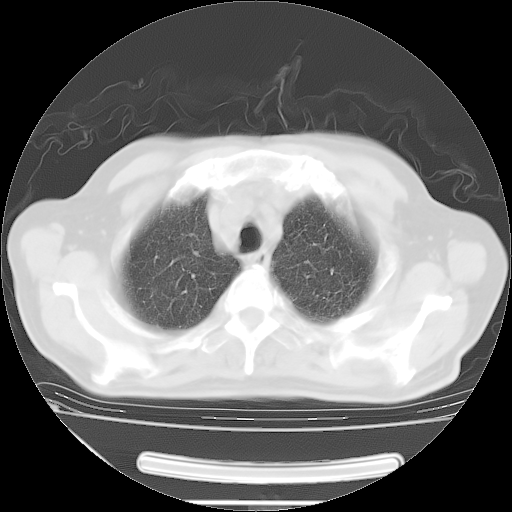

今天复查肺部CT,发现双肺广泛磨玻璃样改变。所以我把3月19日和5月9日相隔50天的肺部CT上传。请大家会诊。

2009年3月19日肺部CT片。

2009年3月19日肺部CT

胸腹部CT,诊断意见:左上肺叶钙化灶、左侧胸膜局限性增厚并钙化、胆囊炎。描述部分肺组织呈磨玻璃样改变。